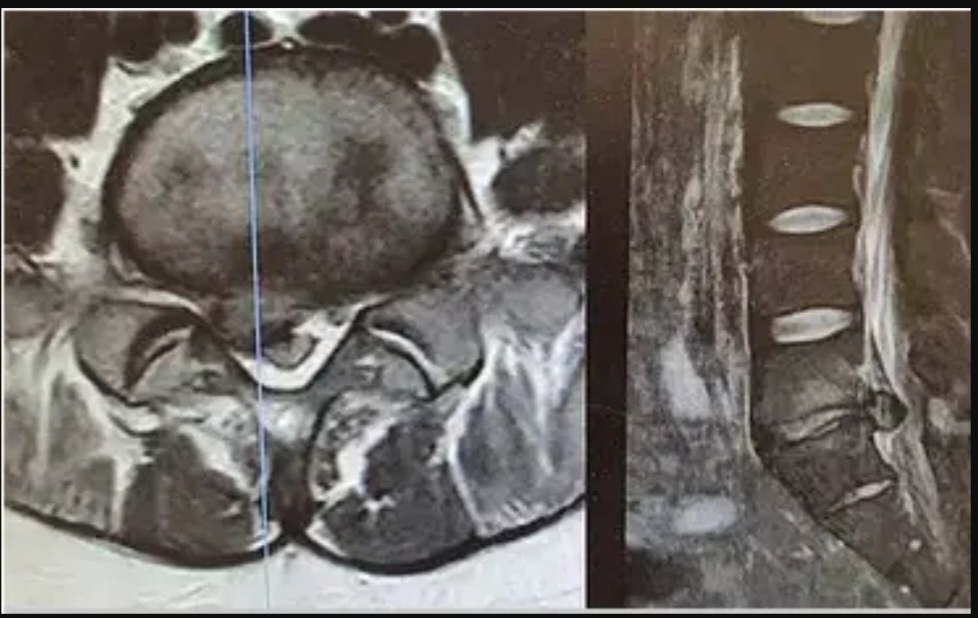

Hérnia de disco: quando o disco pressiona o nervo

A hérnia de disco ocorre quando o disco intervertebral se desloca e comprime uma raiz nervosa. Os sintomas podem incluir:

-Dor intensa, geralmente unilateral

-Irradiação para pernas e pés

-Formigamento, dormência, sensação de agulhadas

Dor que piora com tosse, espirro ou evacuação

-Melhora com repouso em flexão

Hérnia Discal Lombar

No exame físico, observa-se alterações da força muscular, dos reflexos e da sensibilidade, além de sinais de irritação nervosa correspondente a raiz comprometida.